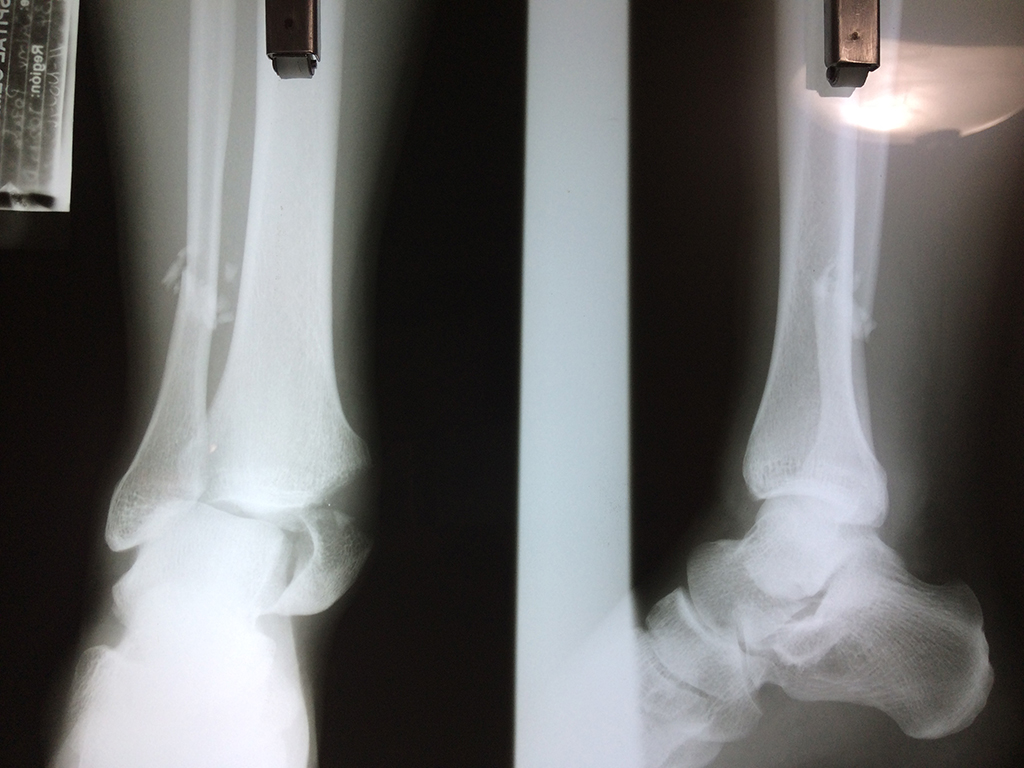

Una fractura de tobillo es la rotura de uno o más de los huesos del tobillo. Estas fracturas pueden ser:

- Parciales (el hueso está sólo parcialmente fisurado, no del todo).

- Completas (el hueso está perforado y está en 2 partes).

- Producirse en uno o ambos lados del tobillo.

Algunas fracturas de tobillo pueden requerir cirugía si:

- Los extremos de los huesos están desalineados entre sí (desplazados).

- La fractura se extiende hasta la articulación del tobillo (fractura intra-articular).

Cuando se necesita cirugía, es probable que esta implique el uso de clavijas de metal, tornillos o placas para sostener los huesos en su lugar mientras la fractura se consolida. Los elementos de soporte pueden ser temporales o permanentes.